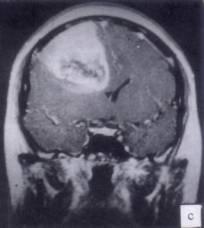

问题 病历摘要:??患者男性,52岁。头痛伴呕吐2月,呕吐呈喷射性。既往身体健康。体检:神清,表情淡漠,反应迟钝,双眼底视神经乳头明显水肿,左鼻唇沟稍浅,左腹壁反射减弱,左上下肢肌力4级,左Babinski征(-)。 根据病史、MR结果,首先考虑哪种诊断?提示:患者行头颅?MR检查(见图)

选项 A.右额叶胆脂瘤 B.右额叶转移瘤 C.右额叶胶质瘤 D.右额叶淋巴瘤 E.右额叶脑膜瘤 F.右额叶脑脓肿 G.右额叶炎性肉芽肿

答案 C